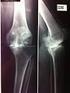

GINOCCHIO DOLOROSO Semeiotica radiologica normale e patologica.

GINOCCHIO DOLOROSO Semeiotica radiologica normale e patologica www.fisiokinesiterapia.biz DIAGNOSTICA PER IMMAGINI ECOGRAFIA RX TOMOGRAFIA COMPUTERIZZATA RISONANZA MAGNETICA ECOGRAFIA Cavo popliteo SI

PROIEZIONI RADIOLOGICHE.

UNIVERSITA POLITECNICA DELLE MARCHE Facoltà di Medicina e Chirurgia Corso di Laurea in Tecniche di Radiologia Medica, per Immagini e Radioterapia PROIEZIONI RADIOLOGICHE. Arto inferiore: [1] coscia - ginocchio

L ESAME OBIETTIVO DEL GINOCCHIO Pistoia, 13 dicembre 2014 Dr Pier Giuseppe Zampetti Ospedale San Jacopo Pistoia [email protected] ESAMI STRUMENTALI ESAMI STRUMENTALI RX RMN TC RADIOLOGIA del GINOCCHIO